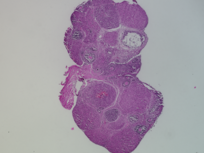

Genus: Mus (mice)

Species: Mus musculus ()

Life Stage: prepubertal

Age: 0 years, 25 days

Accession #: MDB0000582

Ovary position: unspecified

Location: wholeOvary

Section thickness: 5 microns

Fixation: neutralBufferedFormalin10

Stain: Hematoxylin and Eosin

Immunohistochemistry: None

Experimental treatment: Control - mock treatment - PBS, IP injection, 5 days

Other pathology: None